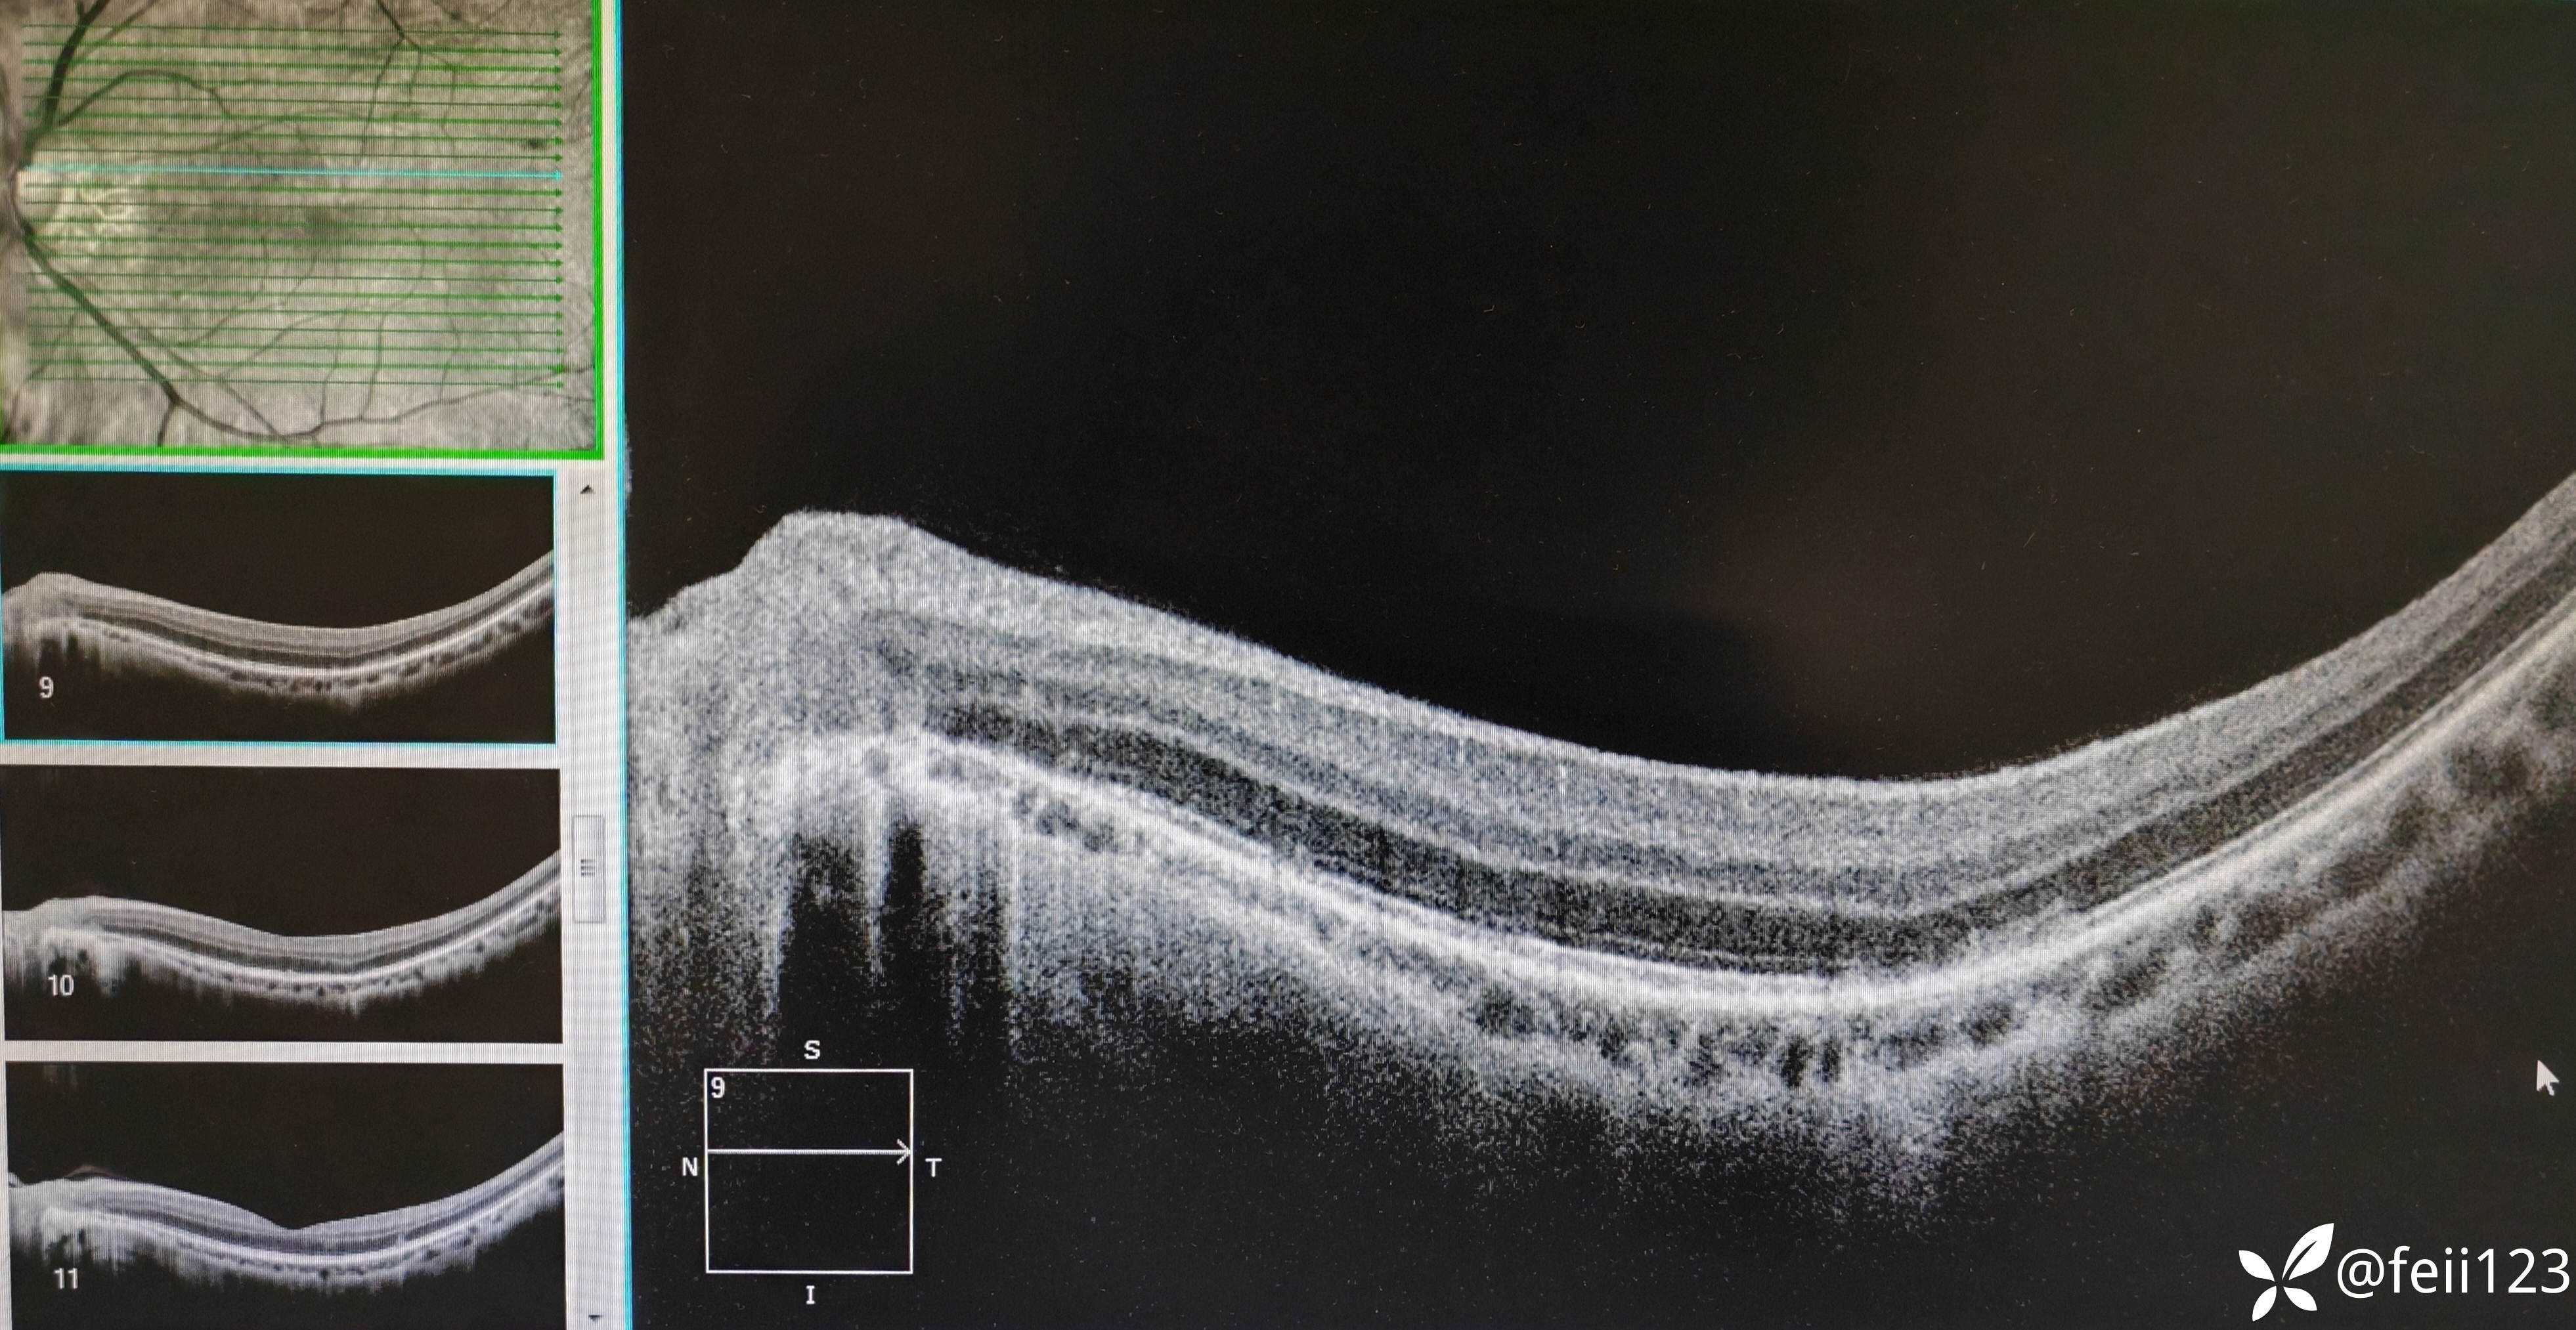

【检查】矫正视力右眼1.0左眼0.4,眼压正常15 16,眼前段未见异常,玻璃体清,眼底如图,左眼底可见后极部及鼻侧周边多个白点。